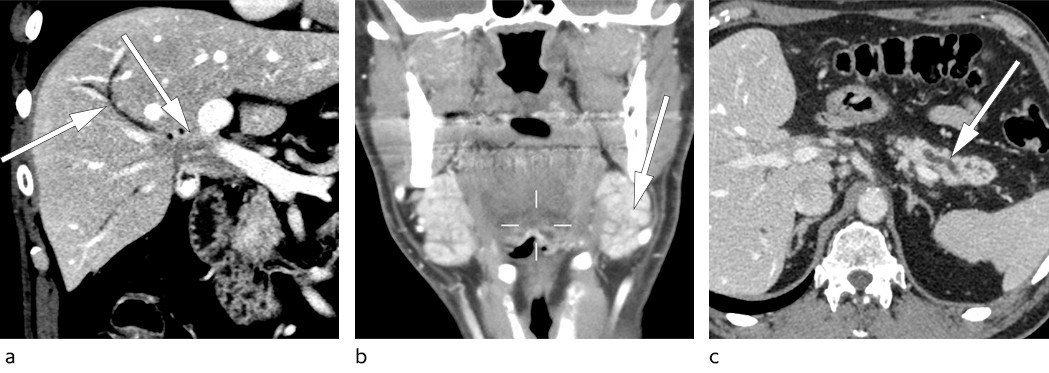

Pasienten kom til poliklinisk konsultasjon dagen etter mottatt henvisning. Det hadde nå gått åtte måneder siden symptomdebut. Ved undersøkelse var blodtrykket 150/105 mm Hg og pulsen 73 slag/min. Pasienten hadde lymfadenopati med 4 × 3 cm store glandler på begge sider av halsen og en mindre lymfeknute i venstre lyske, som ble vurdert til å sannsynligvis være patologisk. Allmenntilstanden fremstod lett redusert. Pasienten ble utredet med CT-lymfomprotokoll, som viste en stor, diffus oppfylning i leverhilum som vokste inn i ductus hepaticus communis (figur 1a). Glandlene på halsen ble beskrevet som fyldige submandibulære spyttkjertler og var ikke metastasesuspekte (figur 1b). Pankreas var atrofisk som ved tidligere MR-undersøkelse (figur 1c). Funnet ga sterk mistanke om et perihilært kolangiokarsinom.

Kolangiokarsinomer kan oppstå i alle segmenter av galletreet og er en sjelden kreftsykdom i den vestlige verden med en insidens på rundt 1–2 per 100 000 (3).

Primær skleroserende kolangitt er den viktigste risikofaktoren, men de fleste kolangiokarsinomer oppstår sporadisk. Perihilære kolangiokarsinomer er den vanligste typen og oppstår nær konfluens av høyre og venstre hovedgallegang (3). Perihilært kolangiokarsinom kalles også Klatskin-tumor etter legen Gerald Klatskin, som beskrev tilstanden for over 50 år siden (4). Diagnosen stilles som regel sent, og 90 % av pasientene debuterer med stille ikterus. Prognosen ved kolangiokarsinom er svært dårlig med femårsoverlevelse for hele gruppen på mindre enn 20 %. Den eneste kurative behandlingen er kirurgi, men bare 25–30 % av pasientene ansees som operable på diagnosetidspunktet (3). Tendensen de siste årene går mot mer aggressiv kirurgisk behandling og inkluderer levertransplantasjon for strengt utvalgte pasienter.